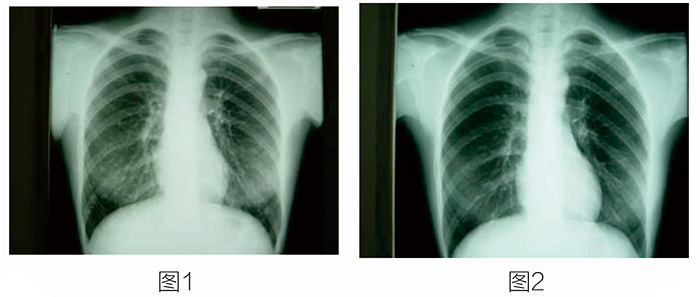

放射性核素治療開展得最早、應用得最廣泛的就是碘-131治療甲狀腺癌及其轉移灶,其它項目還有放射性核素治療癌癥骨轉移等。 這是一位34歲的女性,有甲狀腺乳頭狀腺癌。圖1示雙肺多發(fā)轉移。圖2是口服碘-131治療七次后,雙肺轉移灶完全消失。